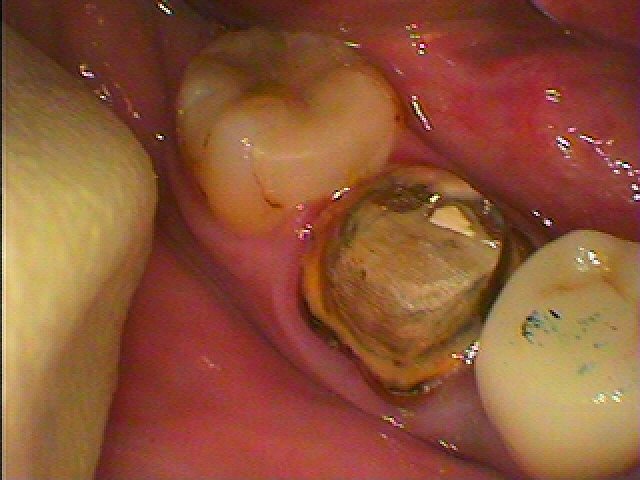

この昔被せた歯も中の根の治療から見ていきます

20年前に治療したそうです

被せを外していきました

土台を外すと中は腐敗していました

可及的におきれいにしていきます

最終的に薬を詰めていきました

このまま放置していたらいつかはインプラントした歯のように

割れてきて抜歯となったことでしょう